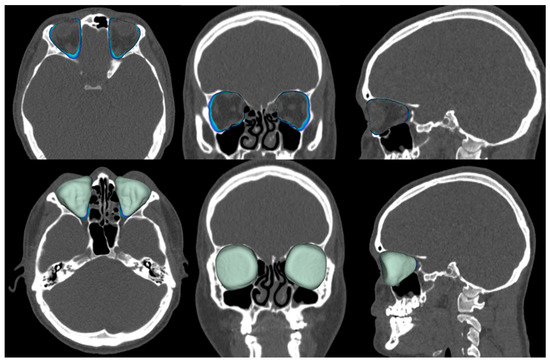

Figure 3.

Assessment of the volume of the bony orbit in the cleft group. Top row contours, and bottom row colors.